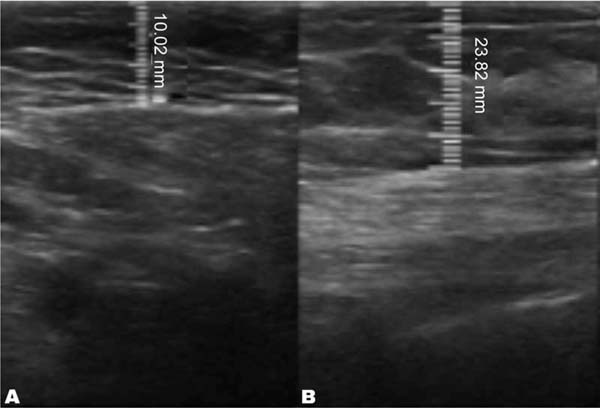

The measurement of subcutaneous tissue thickness is performed vertically, from the highest (right at the transition from the epidermis) to the lowest point (at the transition with the muscle tissue) of subcutaneous tissue thickness. This measurement is easily reproducible for those with basic ultrasound skills (►Fig. 2). In lipofilled breasts, the thickness of subcutaneous tissue was measured preoperatively and immediately after lipofilling, as well as at 15, 30, 90, and 180 days postoperatively. Measurements in millimeters were taken using ultrasound, including the vertical distance from the highest (closest to the epidermis) to the lowest point (closest to the adjacent musculature) of the subcutaneous tissue at the previously defined point. A GE LOGIQ P6 (GE HealthCare) ultrasound device with an 11L linear probe and a frequency range of 12 to 6 MHz was used, operated by a surgeon with postgraduate training in general ultrasonography (►Fig. 3).

In the decanted graft group, the average reduction compared with the initial thickness after lipofilling was 9.90% on day 15, 19.27% on month 1, 23.59% on month 3, and 26.36% on month 6. In the filtered graft group, the average reduction compared to the initial thickness after lipofilling was 7.74% on day 15, 14.85% on month 1, 20.67% on month 3, and 22.80% on month 6 (►Fig. 6). ►Figs 7–8 reveal the ultrasound change in subcutaneous tissue’s thickness before and after lipofilling. ►Figs. 9–10 show the pre-and postoperative results of one patient from each group.